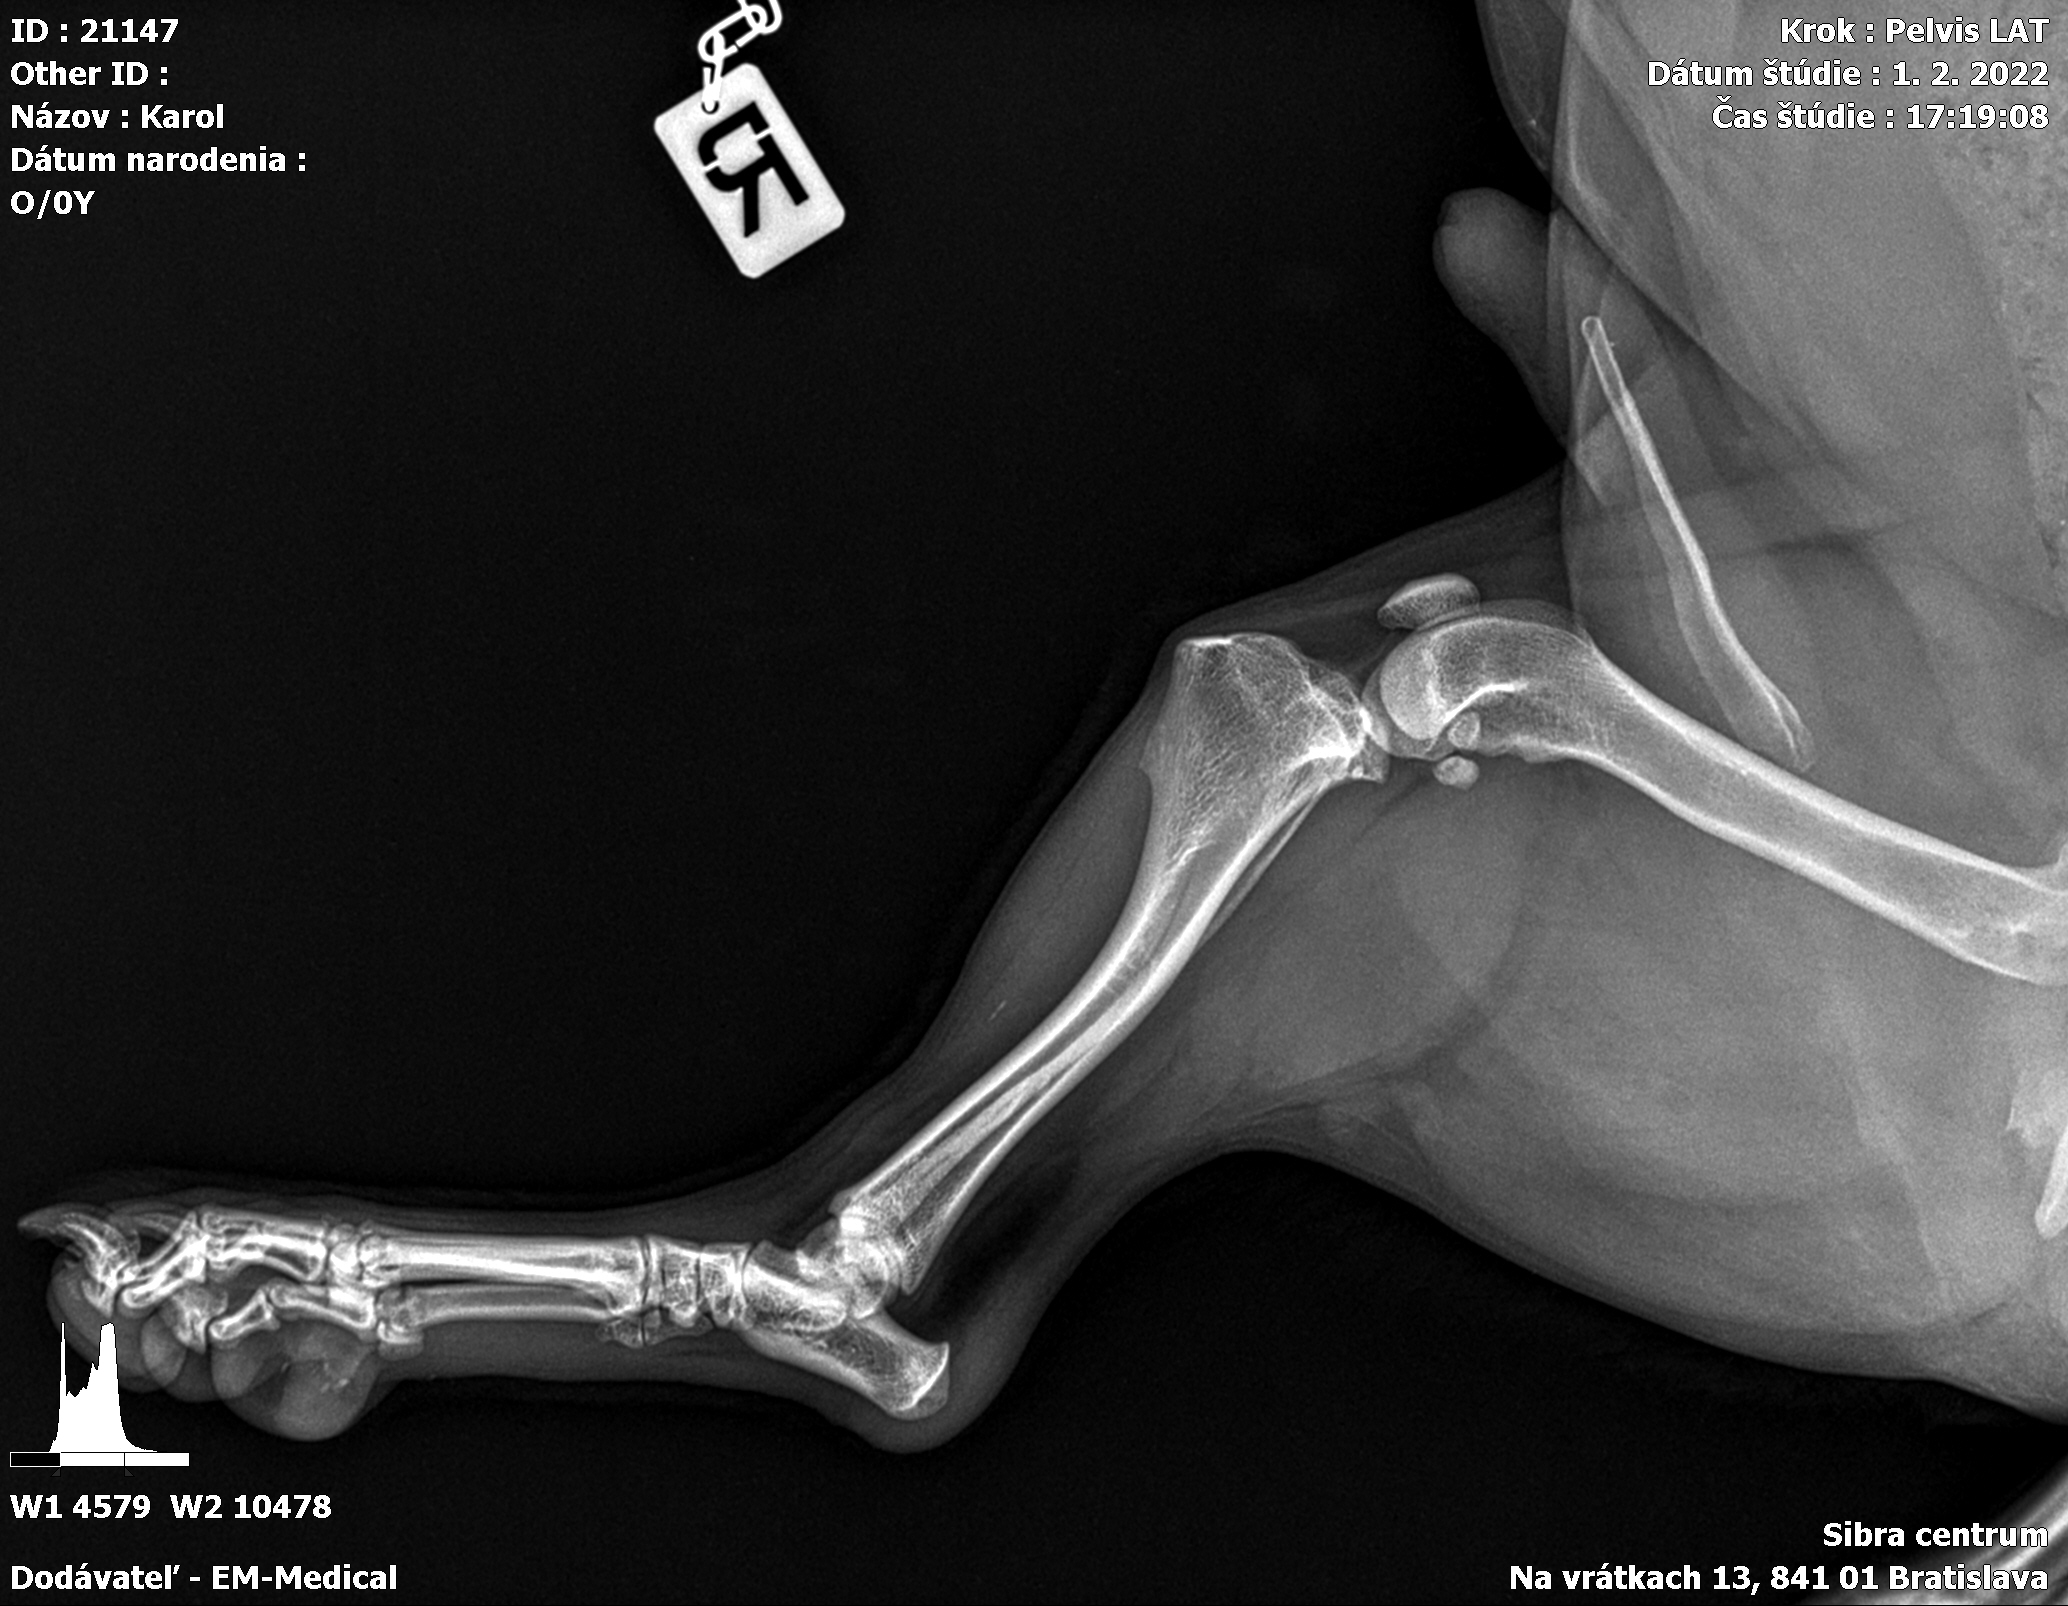

Karola nám doviezla pani, ktorá ho našla, asi jediná dobrá duša, ktorá pri ňom neprešla so zatvorenými očami. Ihneď sme s krpcom utekali na veterinu aby sa zistila závažnosť jeho zranení. Hneď pri prvých RTG snímkoch sa ukázala obojstranná fraktúra panvy, taktiež fraktúra krídla panvy a keby mu to chudákovi nestačilo, do tretice sa objavila zlomenina stavca. Karolko mal neznesiteľné bolesti, ale krásne prečkal vyšetrenie lebo vedel, že je v dobrých rukách a dostáva sa mu pomoci. Po nálezoch sme okamžite kontaktovali neurológiu a ortopédiu na veterinárnej klinike Sibra - centrum veterinárnej medicíny, kde sme dostali hneď termín na príjem.

Karol nemá žiadne neurologické deficity, po ortopedickej operácii bude vedieť behať a bez problémov bude vedieť samostatne cikať a kakať. Po tejto úžasnej správe sme samozrejme dali zelenú náročnej ortopedickej operácii pod vedením MVDr. Vatolíka. Operácia sa podarila na výbornú, Karči je "zoskrutkovaný" a vôbec nič mu nebráni v tom, aby opäť mohol behať a aktívne žiť. Momentálne sa zotavuje po operácii, musí mať prísny kľudový režim. Po vybratí stehov ho čaká hydro- a fyzioterapia, ktorá mu pomôže postaviť sa na nohy. Je to bojovník, veľmi sa chce uzdraviť a v jeho očkách je dokonale vidieť, že už kuje plány čo všetko zameškané bude musieť dobehnúť.